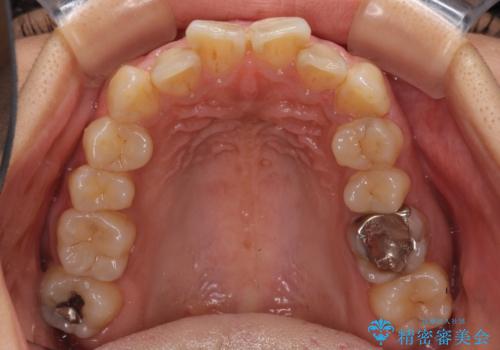

デコボコと口元の突出感 ハーフリンガルでの抜歯矯正

- 前歯のデコボコと上顎の前突感による口の閉じにくさを気にして来院された患者様です。

目立たない装置を希望されたので、上顎が裏側装置のハーフリンガルを選択し、上下左右の小臼歯(計4歯)を抜歯して矯正治療を行うこととしました。